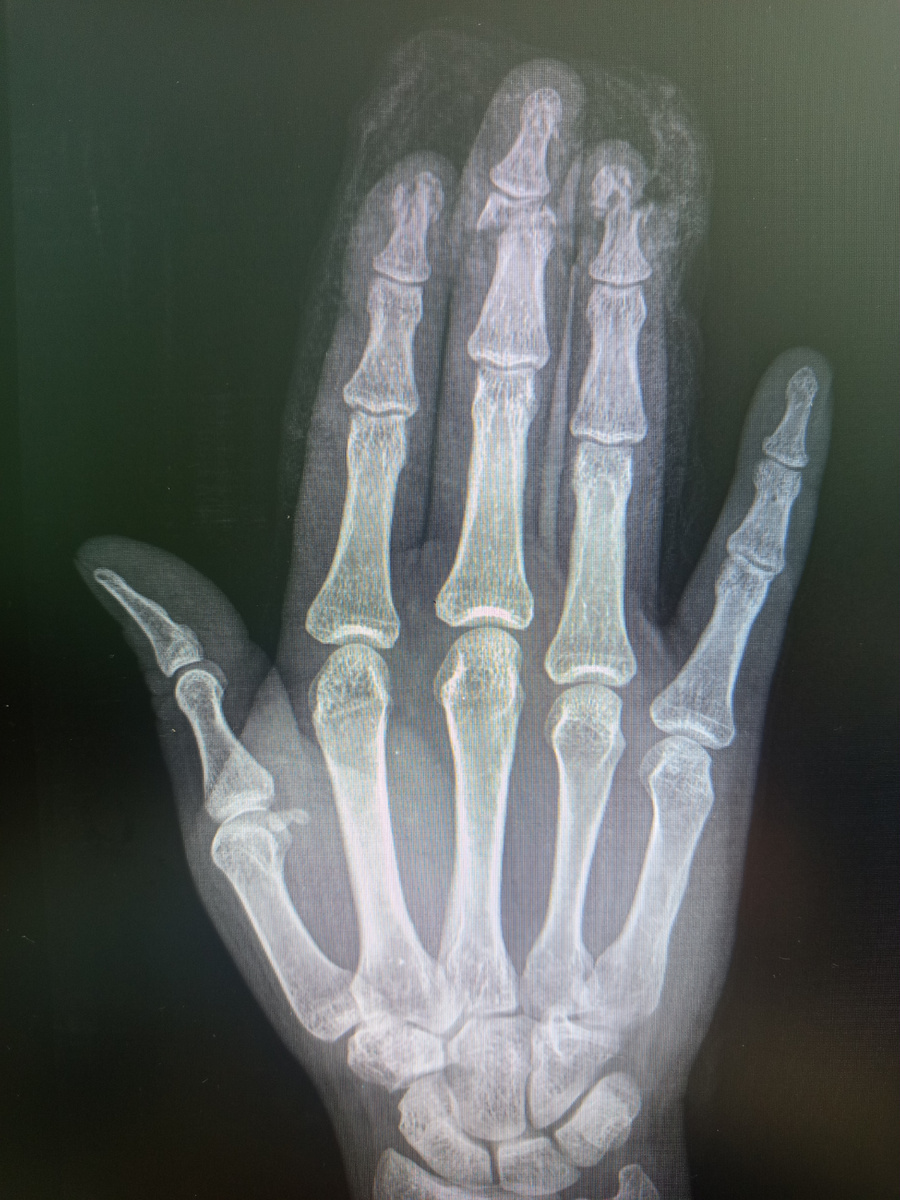

Потом потихоньку народ стал идти. Не поверите , шли с поврежденными конечностями

Вот пришел с производственной травмой молодой индус. По- русски не разговаривает совсем , но с ним сопровождающий , мужчина средних лет .

В станок какой-то руку засунул.

Вот пришел на контроль. Странное решение , четвертый палец почистили , а второй и третий оставили так и даже без гипса, немного сопоставили и , загипсованы отправили домой . Возможно , проблемы с документами, у нас так было , у пациента не было документов , ему первую помощь оказали и отправили восвояси, пошёл он на госпитализацию только через три дня , собрав необходимый пакет документов.

А вот пациент , 43 года, помогал другу с переездом , палец повредил об механизм дивана.

Пошел к травматологам , и вернулся позже на контроль.

–Нет , сказали , что нечего спасать, все вхлам.

Дедуля пилил дома доски.

Как ни странно , но дедуле поставили в палец спицу.

Снова мужчина , снова на кисть , снова на левую.

Шутит , что пальцы бывают немного лишними.

–Как думаете , спасут или придут к выводу , что лишний? –шутливо спрашивает пациент.

Вернулся на контроль.

–Нет , пришли к выводу , что лишний! Сказали , что все сосуды перебиты и нет смысла , и стал у меня палец сегодня короче на две фаланги.